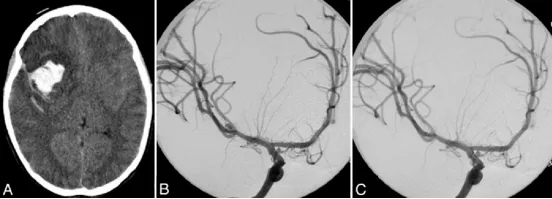

图1. A:头颅CT平扫显示右额叶出血,侧裂池内可见高密度蛛网膜下腔出血;B:右侧颈内动脉造影斜位片提示大脑中动脉(MCA)三分叉处存在一直径5毫米的动脉瘤;C:右侧颈内动脉造影斜位片显示MCA动脉瘤经血管内弹簧圈栓塞术后状态。